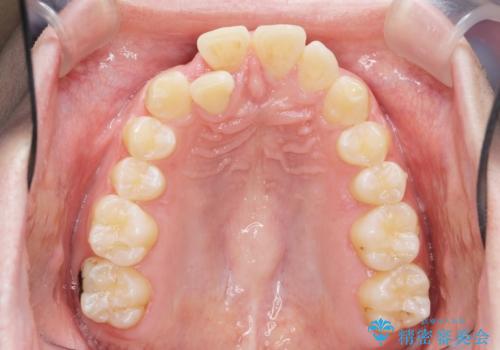

前歯が隠れていて見えない クロスバイトの矯正治療

- 「前歯が1本隠れていて見えない、歯並びを矯正治療で改善したい。」と希望され来院されました。

奥に隠れている前歯を並べられるスペースを確保したのち、歯並びを整えていきます。

前歯のスペース不足により1本だけ後方に位置している状態でしたが、しっかりとスペースを確保し配列することができました。